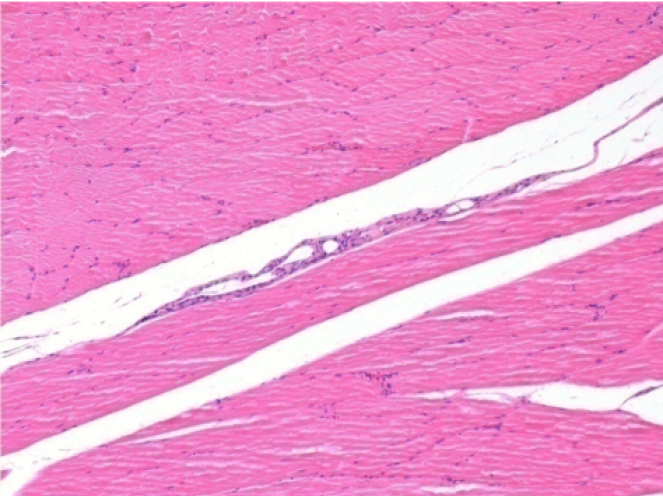

L:Pretibial-No treatment

R:Pretibial-After 0.1 ml NaCl 0.9% IM

- كان لذى الصندوق الاول مجموعة التحكم حيث تلقو تطبيق 0.1 مل من محلول ملحي (NaCl 0,9%) في عضلة مقدم الضنبوب اليمنى.